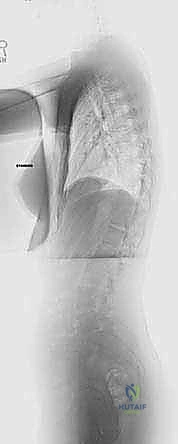

- الأشعة السينية الكاملة للعمود الفقري (Full Spine X-Rays):

- صور أمامية خلفية (AP) وجانبية (Lateral) والمريض واقف.

- يتم من خلالها قياس زاوية كوب (Cobb Angle)، وهي المعيار الذهبي لتحديد شدة الانحناء.

- أشعة الانحناء الجانبي (Side-Bending Films) وأشعة الشد (Traction Films):

- هذه الصور حاسمة جداً. يُطلب من المريض الانحناء لأقصى درجة يميناً ويساراً أثناء التصوير.

- الهدف هو تقييم "مرونة" الانحناء (Flexibility). إذا لم يتعدل الانحناء كثيراً في هذه الصور، فهذا يعني أن الانحناء "صلب" (Rigid)، وهذا هو المؤشر الرئيسي للحاجة إلى جراحة التحرير الأمامي.